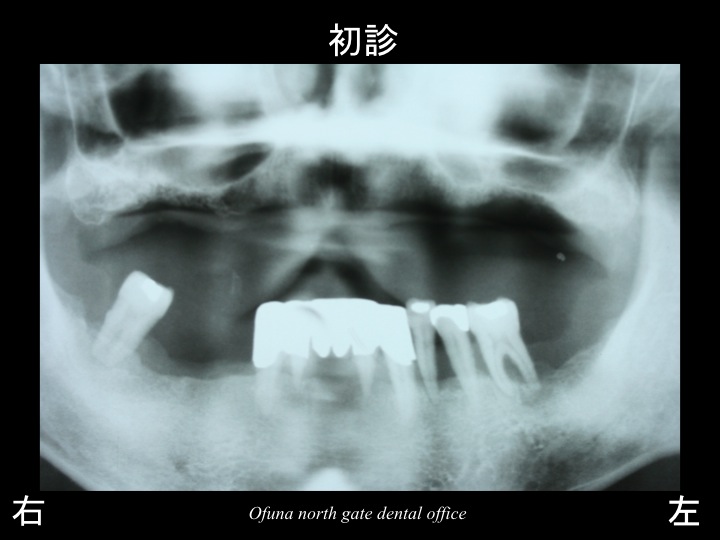

初診のレントゲンは古いものですので、写りが悪いですが…

以下が初診時になります。

初診時上顎は歯が1本もありませんでした。

下の歯もグラグラしていました。